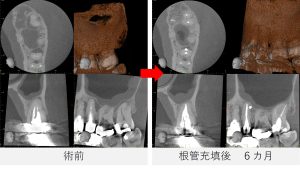

根管充填後から6カ月

- 痛みはなく、鼻のにおいなどの症状も認められませんでした。

- レントゲンおよびCTで確認したところ、根の先や側面に見られていた透過像は縮小し、骨の回復傾向が確認されました。

- 特に、根の側面に見られていた透過像は、歯の根の途中から分かれている細い枝状の通路(側枝:そくし)に関連した炎症であった可能性が考えられます。

- 歯の根の内部は必ずしも一本のまっすぐな管だけではなく、途中で枝分かれしている細い通路が存在することがあります。

こうした側枝に感染が及んでいる場合、レントゲンやCTでは根の側面に黒い影として見えることがあります。

- 今回の症例では、根管治療後の経過観察でその透過像が縮小し、骨の回復傾向が確認されました。

- 炎症の改善がみられたため、最終補綴(被せ物の作製)へ移行する予定としました。